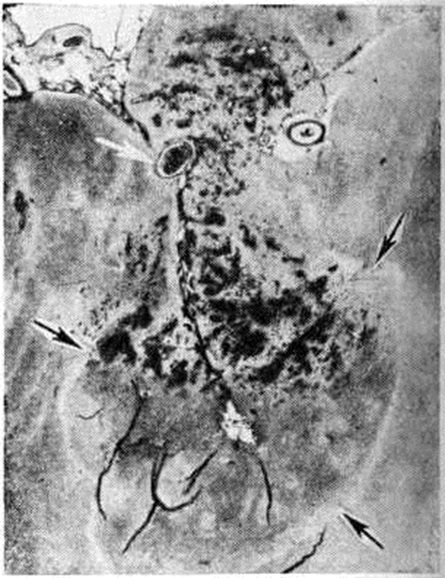

Геморрагический инсульт, как правило, возникает при заболеваниях, протекающих с повышенным артериальное давление. Это обусловлено тем, что сосудистые кризы (смотри полный свод знаний), характерные для гипертонической болезни (смотри полный свод знаний) и артериальной гипертензии (смотри полный свод знаний Гипертензия артериальная), приводят к морфологический изменениям стенок внутримозговых сосудов с нарушением их проницаемости — плазматическому пропитыванию (рисунок 1), некрозам (рисунок 2), образованию микроаневризм (рисунок 3) и их разрывам. Разрыв врождённых артериальных и артериовенозных аневризм может протекать на фоне нормального давления. Преимущественная локализация и характер геморрагий определяются особенностями ангиоархитектоники различных отделов мозга. При гипертонической болезни наиболее тяжёлым изменениям подвергаются сосуды подкорковых узлов и зрительного бугра. Это объясняется отхождением глубоких ветвей под прямым углом от средней мозговой артерии, являющейся продолжением внутренней сонной артерии, и незначительным числом анастомозов сосудов в этой области. В связи с этим на вскрытии кровоизлияния наиболее часто (40%) обнаруживаются в подкорковых узлах с распространением в прилежащее белое вещество (так называемый латеральные кровоизлияния, то есть расположенные латерально от внутренней капсулы, рисунок 4). Второе место по частоте (16%) занимают обширные кровоизлияния, разрушающие подкорковые узлы, внутреннюю капсулу, зрительный бугор (так называемый смешанные кровоизлияния — рисунок 5). Кровоизлияния в зрительный бугор (так называемый медиальные — рисунок 6) составляют 10%, в мозжечок — 6—10%, в мост мозга — 5% от общего числа внутримозговых геморрагий. Кровоизлияния только в белое вещество полушарий мозга встречаются крайне редко. Подразделение полушарных кровоизлияний на латеральные, медиальные и смешанные имеет особое значение в связи с хирургическим лечением геморрагического Инсульт.